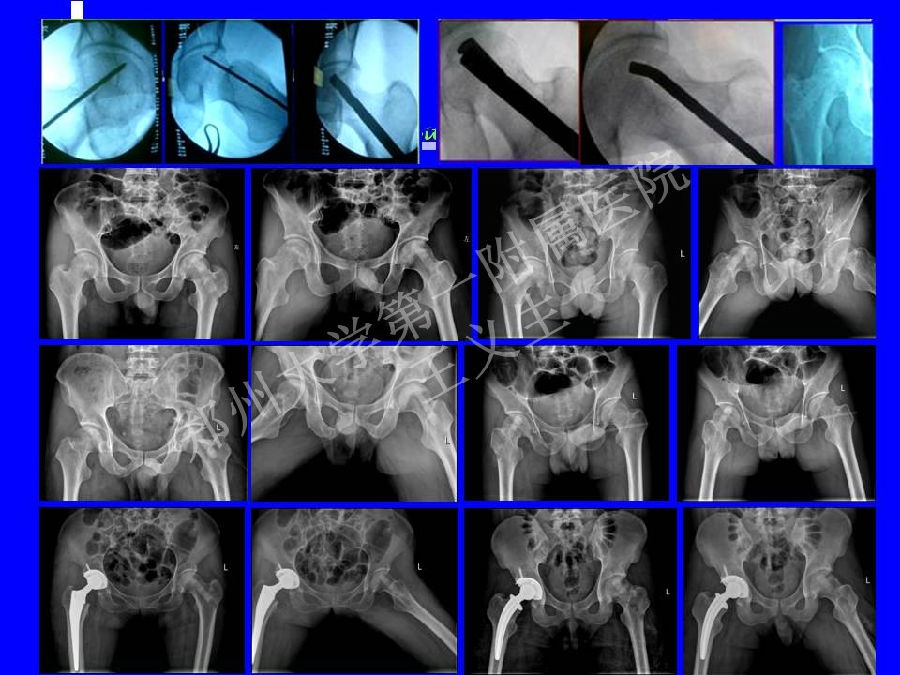

2014-04-24 文章来源:郑州大学第一附属医院骨科 王义生 我要说